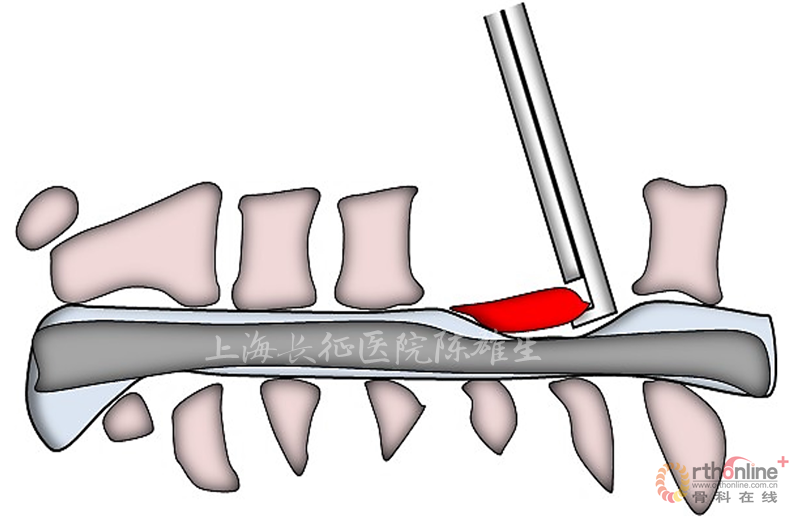

1.2骨化物打磨成薄片后分块切除

次全切除OPLL表面的椎体,使用磨钻等工具将骨化物打磨成薄片,然后逐渐游离骨化物,分块将之切除。该方法适用于骨化物椎管占有率>50%,骨化物与硬膜囊无粘连或粘连轻。(图2)

图2